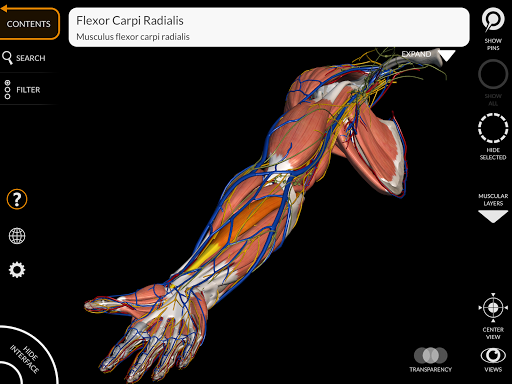

من خلال واجهة بسيطة وبديهية، من الممكن ملاحظة كل بنية تشريحية من أي زاوية.

تتميز النماذج التشريحية ثلاثية الأبعاد بتفاصيل خاصة ودقة تصل إلى 4K.

• تدوير وتكبير كل نموذج في مساحة ثلاثية الأبعاد

• تصور العضلات من خلال مستويات الطبقات من الطبقات السطحية إلى الأعمق

• من خلال تحديد نموذج أو دبوس، يظهر المصطلح التشريحي ذي الصلة

• وصف العضلات: الأصل والإدخال والتعصيب والعمل